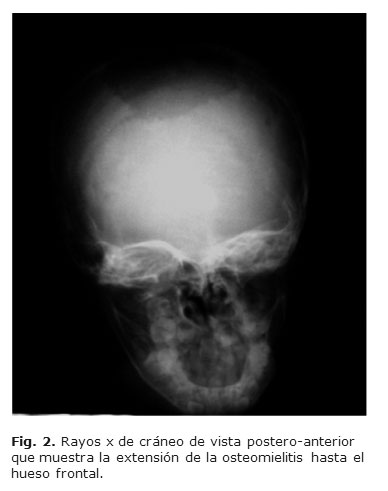

Al examen físico se constató un aumento de volumen con fluctuación de dicha región, dolor a la palpación y defecto óseo irregular. Se realizó examen de Rayos x de cráneo de vista lateral y postero-anterior, donde se pudo observar la lesión osteolítica de la bóveda craneal, localizada en región interparietal que se extendía al hueso frontal y occipital. (Figuras 1 y 2)

Las características imagenológicas son sumamente inespecíficas y muestran destrucción ósea focal, pudiendo confundir con otras patologías como el granuloma eosinófilo, quiste óseo aneurismático, metástasis, mieloma múltiple o hemangiomas. La tomografía axial computarizada es útil para evaluar la extensión de la lesión a tejidos blandos (cuero cabelludo) y el compromiso intracraneal. 18 Para el diagnóstico positivo se requiere del examen anatomopatológico de tejido óseo y el crecimiento del bacilo de Köch en los cultivos de secreciones.